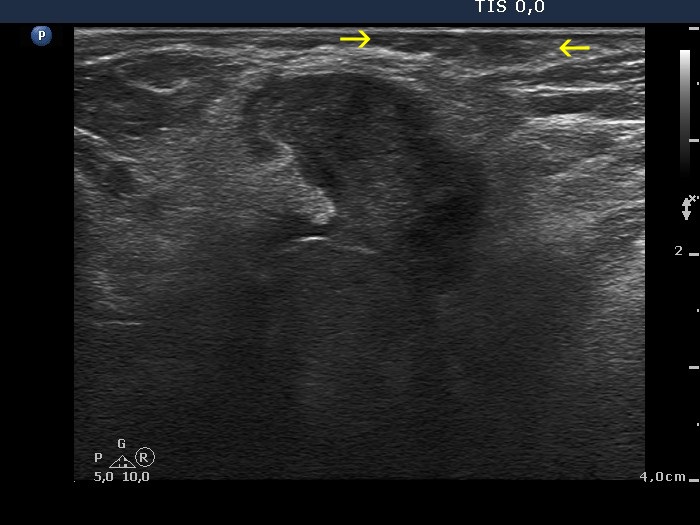

Parathyroid carcinoma (histology) - case 755 |

Transverse scan |

Longitudinal scan |

This is a hypoechoic lesion which proved to be a parathyroid carcinoma which was located in the lower pole of the left lobe. In the transverse view the tumor is brighter than the strap muscle while the situation is opposite in the longitudinal scan.